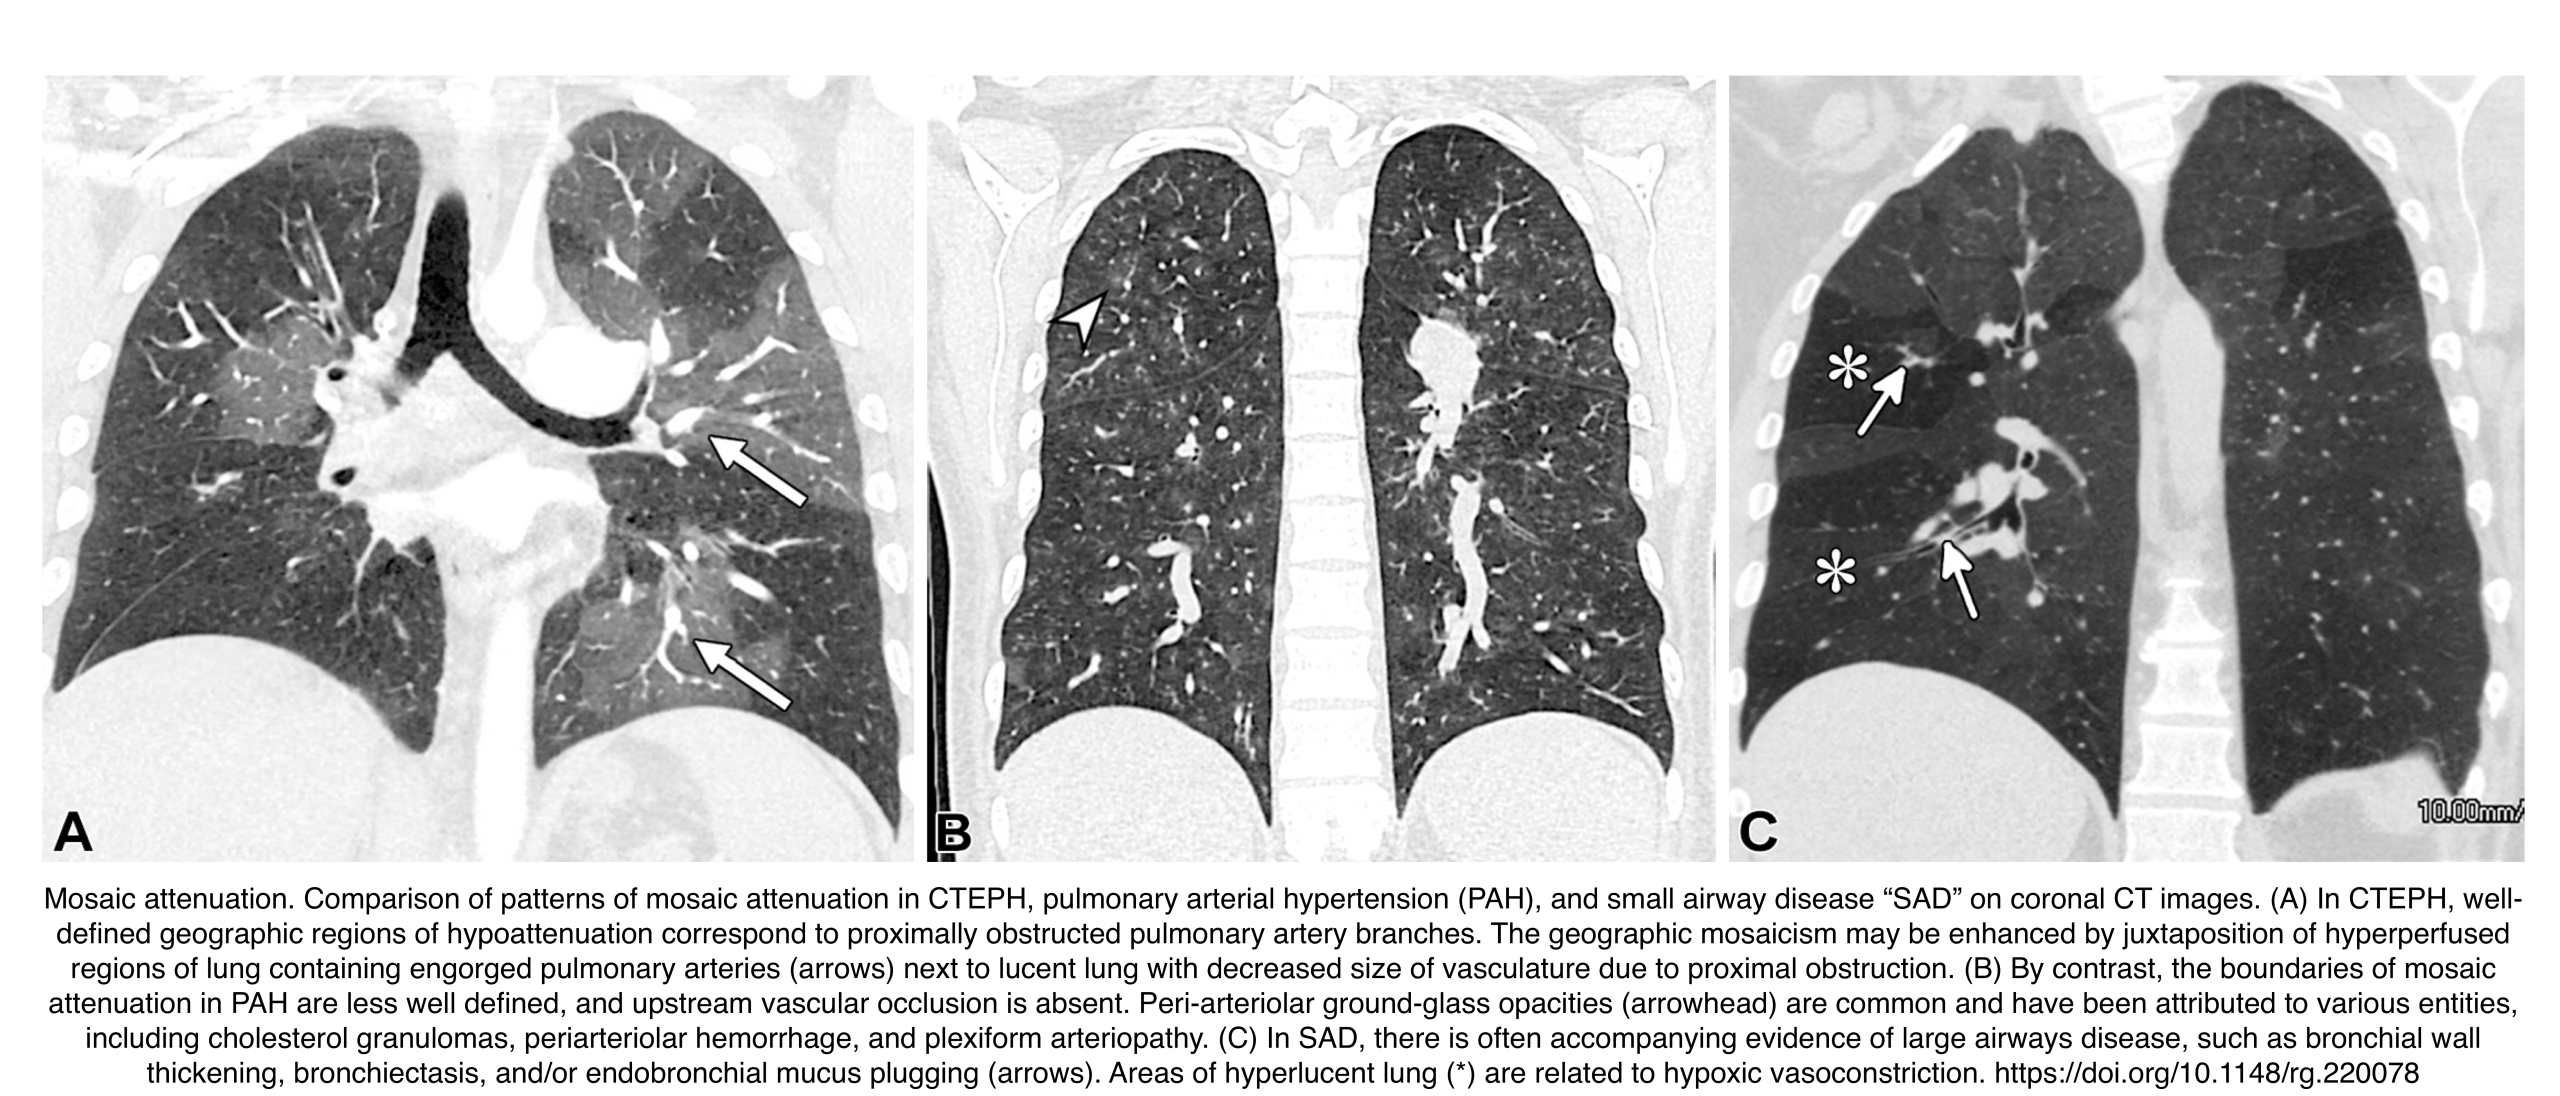

Refers to the geographic pattern of alternating lung opacity and lucency (i.e., heterogeneous lung areas with differing attenuation on CT) *.

- Multiple Potential Causes *

- Small airways disease (bronchiolitis, asthma, bronchiectasis).

- Vascular disorders (chronic thromboembolic hypertension, pulmonary arterial hypertension).

- Alveolar processes (infection, pulmonary edema, organizing pneumonia).

- Imaging clues helpful in pinpointing a diagnosis include evidence of large airway involvement, cardiovascular abnormalities, septal thickening, signs of fibrosis, and demonstration of air trapping at expiratory imaging.

- 💡Key Diagnostic Clue: Compare vessel diameter in lucent vs. opaque areas

- Uniform Vessel Diameter:

- Opaque regions are abnormal.

- Indicates infiltrative processes (infection, edema).

- Non-uniform Vessel Diameter:

- Lucent areas are abnormal.

- Smaller vessels in lucent regions.

- Suggests air trapping or vascular disease.